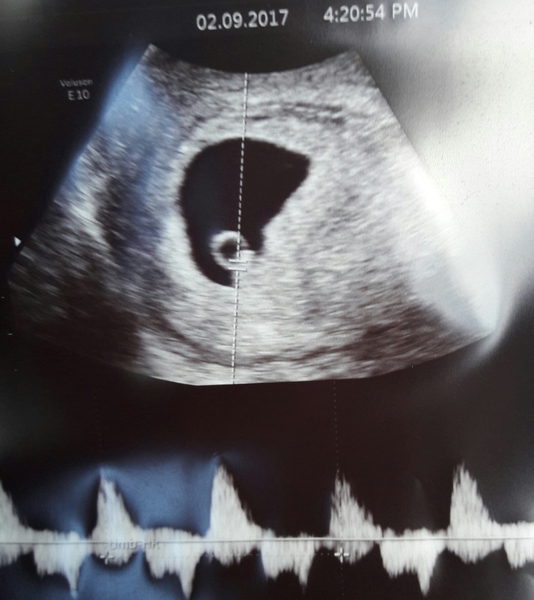

WhyTheHeckMe · 02/09/2017 16:53

Baby is there, with a heartbeat and matching my dates exactly of 6w2d giving me EDD of 26/4/18

I don't feel out of the woods just yet but I am certainly very very relieved. My little rainbow baby Smile

Anyone got any experience of subchorionic haematoma? The sonographer took quite a lot of pics and told me I have a blood clot and showed me and said to mention to mw tomorrow.

Just googled it (damn) and now panicking like mad.

The sack is on the left and the bleed is on the right... anyone? !